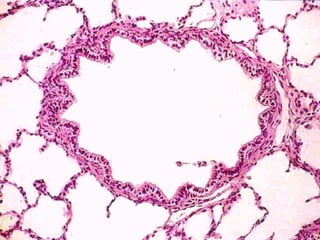

B R O N Q U I O L O S MUCOSA Epitelio de simplecilíndrico cccc hasta cúbico con cilios sin células caliciformes, con células de Clara Tejido conectivo laxo Mas pliegues que en bronquios Músculo liso, relativamente más gruesa que en los bronquios Tejido conectivo laxo, muy fina hasta casi desaparecer en los bronquiolos terminales MUSCULAR ADVENTICIA

T A B I Q U E Epitelio simple planoalveolar y su lámina basal Tejido conectivo laxo: fibras reticulares y elásticas finas y abundante red capilar Epitelio simple plano alveolar y su lámina basal I N T E R A L V E O L A R

Neumocito tipo I(célula plana) Neumocito tipo II (célula alveolar) Células endoteliales Macrófagos alveolares Células sanguíneas (dentro de los capilares) Fibroblastos C É L U L A S D E L T A B I Q U E I N T E R A L V E O L A R